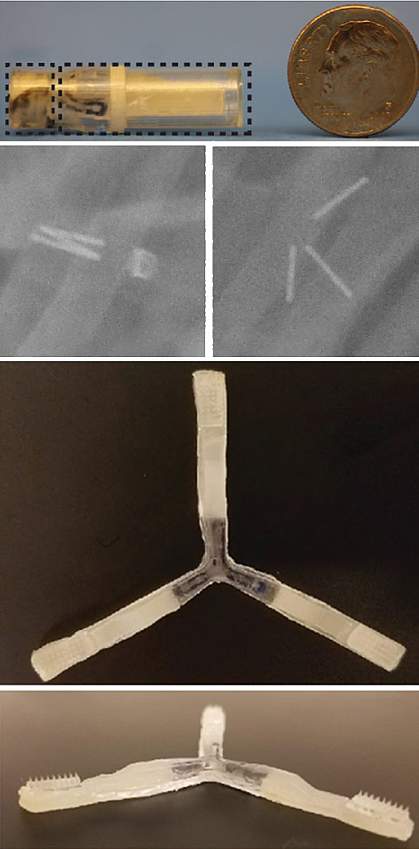

The team developed an ingestible capsule they named the “luminal unfolding microneedle injector” or LUMI. The device is roughly the size of a pen cap, measuring 9 mm (.35 inches) in diameter and 30 mm (1.2 inches) in length.

The capsule protects the LUMI during the acidic journey through the stomach and ejects the LUMI when it reaches the small intestine. Three spring-loaded arms extend, pushing a cluster of 1-mm long microneedles into the tissue wall of the small intestine. These microneedles dissolve, releasing the medication. The drug is then carried to the bloodstream.